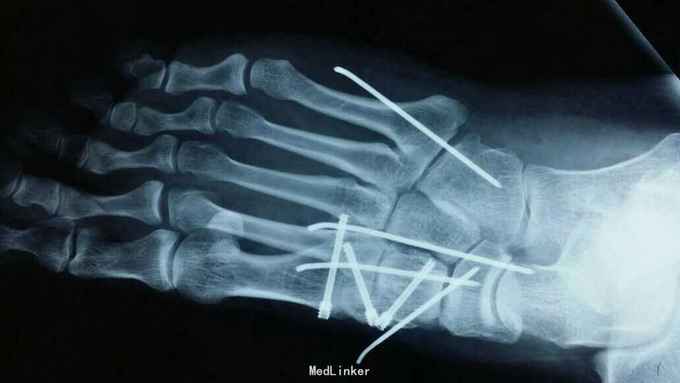

主诉:右足外伤后肿痛,活动受限11天。 现病史:患者于2015年11月10日摔伤右足,当即肿痛,活动受限,急去当地医院拍片及入院行石膏固定保守治疗,效果不佳,为求进一步治疗来诊我院,经门诊阅片及查体后以“右足多发骨折,脱位,韧带损伤”为诊断收入院。

查体:右足略肿胀,畸形明显,足背压痛广泛阳性,可触及骨擦音及骨察感,活动受限,末梢各趾活动自如,足背动脉清。 辅助检查:大致正常。

诊断:右足多发骨折伴跖跗关节脱位,韧带损伤 治疗:患者入院后,完善检查,于2015年11月25日行手术治疗,现切口愈合良好。